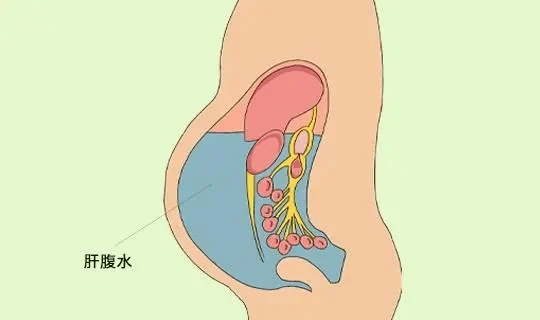

峨眉仙山,人杰地灵。经过几千年的沉淀,留下了许多养生医药传承的艺术奇葩,其中廖氏利水法就是传承了南宋时期金顶白云禅师编写的《峨眉莲花宝笈》,该法专治肝硬化腹水,后由峨眉山僧人传承给赵银武,赵银武又传其女赵雨银及孙儿廖方平、孙女廖兰英。经过廖氏几代人的反复民间应验,治愈各类肝病患者数以万计。